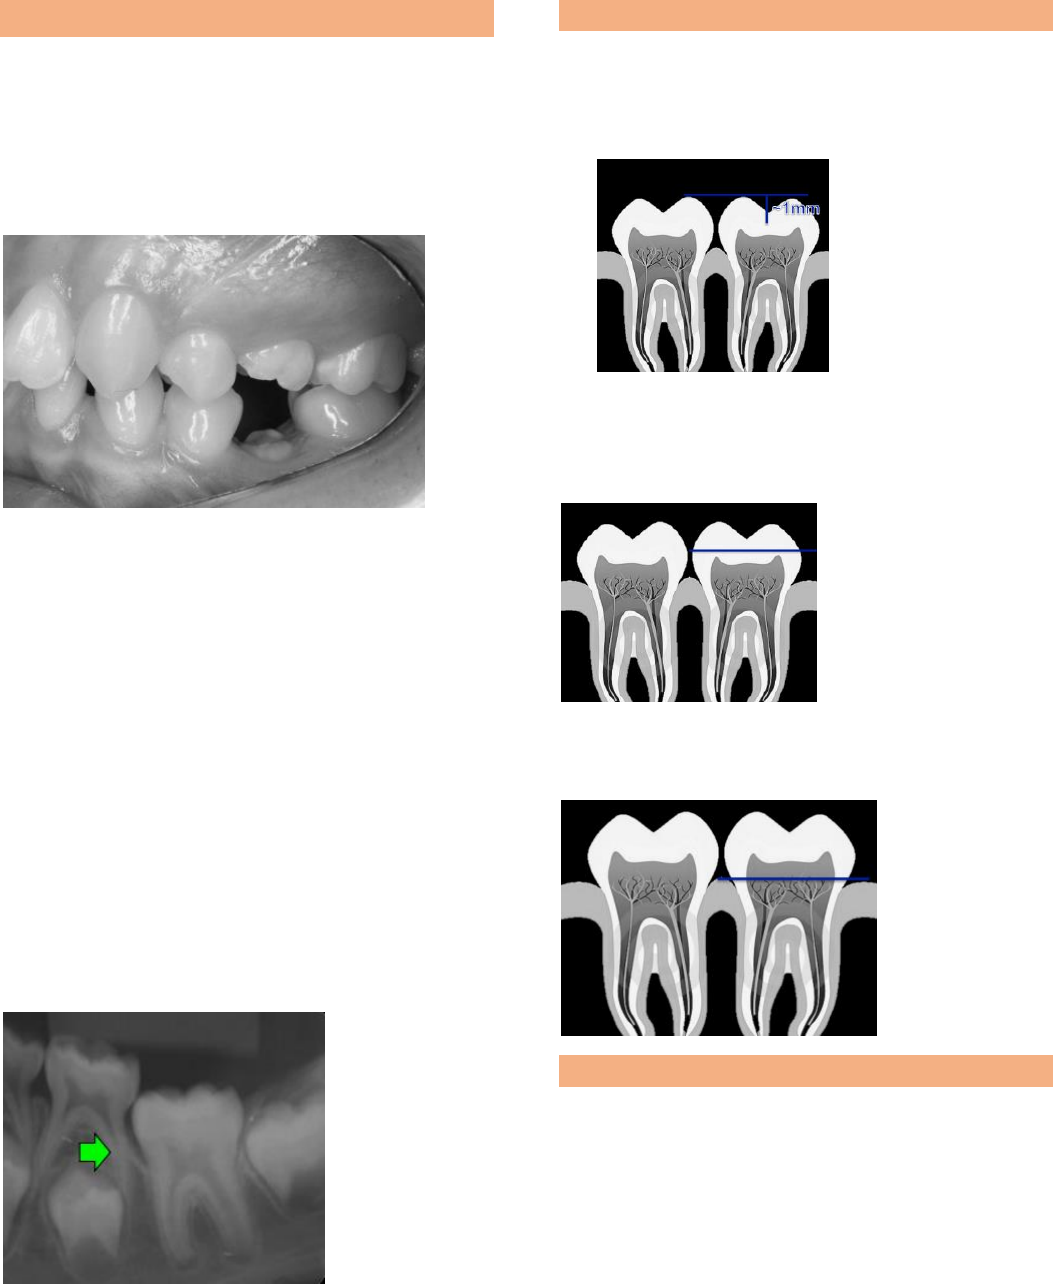

<p>ANQUILOSE DENTÁRIA:</p><p>É um processo de reabsorção por substituição do</p><p>ligamento periodontal pelo osso alveolar que se</p><p>fusiona à dentina e ao cemento.</p><p>Em uma condição clínica para estabelecer se é</p><p>uma anquilose, deve-se avaliar a infraoclusão</p><p>em uma radiografia não há lâmina dura, e o</p><p>dente pode ter anquilose em áreas diferente, não</p><p>em todo o ligamento.</p><p>Etiologia:</p><p> Idiopatia</p><p> Trauma</p><p> Fatores genéticos</p><p> Distúrbios locais no mecanismo de</p><p>erupção</p><p>Radiografia periapical é o meio utilizado para</p><p>determinar se há anquilose é avaliar nível da crista</p><p>óssea alveolar.</p><p>Lâmina dura desaparece, com defeito ósseo vertical</p><p>Com o dente anquilosado o rebordo fica baixo,</p><p>sendo um problema para colocação de um</p><p>implante.</p><p>CLASSIFICAÇÃO DA ANQUILOSE DENTÁRIA:</p><p> Grau leve: superfície oclusal</p><p>aproximadamente 1mm abaixo da</p><p>superfície oclusal do dente adjacente</p><p> Grau moderado: Seperficie oclusal ao</p><p>nível do ponto de contato dos dentes</p><p>adjacentes</p><p> Grau severo: Seperficie oclusal abaixo do</p><p>tecido gengival interproximal</p><p>IMPLICAÇÕES CLÍNICAS:</p><p>1. Diminuição do perímetro do arco</p><p>2. Extrusão dos dentes antagonistas</p><p>3. Inclinação axial incorreta dos dentes</p><p>adjacentes</p><p>4. Redução no crescimento vertical do processo</p><p>alveolar</p><p>5. Hábitos de interposição de língua</p><p>6. Desvio da linha média</p><p>TRATAMENTO:</p><p>PROSERVAÇÃO: não seria feito nenhum tratamento</p><p>somente acompanhamento, observando a progressão</p><p>do defeito ósseo vertical. Esta é uma opção quando a</p><p>infraoclusão é suave</p><p>REPRODUZIR CONTATO COM ANTAGONISTA: por</p><p>meio de restaurações com resina composta ou até</p><p>mesmo confecções de coroas unitárias.</p><p>SUBLUXAÇÃO/ORTODONTIA: o tratamento</p><p>ortodôntico seguido da luxação pode ser uma</p><p>abordagem que possui fatores de risco como: a</p><p>fratura, a recidiva de anquilose e a necessidade de</p><p>tratamento endodôntico. É utilizado para forçar a</p><p>irrupção do dente em infraoclusão. Indicado para grau</p><p>moderado/grave</p><p>OSTEOTOMIA SEGMENTAR: é um procedimento</p><p>cirúrgico em que o osso alveolar incluindo dente</p><p>afetado é seccionado e reposicionado. Este é indicado</p><p>em casos de infraoclusao leve.</p><p>REMOÇÃO CIRURGICA: Indicado em infraoclusão</p><p>severa e inclinação dos dentes adjacentes, e é</p><p>frequentemente indicada quando a extrusão do molar</p><p>anquilosado não surtiu efeito.se a infraoclusão for</p><p>inferior a 5 mm.</p><p>TUMORES ODONTOMA:</p><p>Os Odontomas são tumores odontogênicos mistos</p><p>pois são compostos de tecido dentário mineralizado</p><p>tanto de origem epitelialquanto mesenquimal.</p><p>Em alguns casos eles impedem a erupção do</p><p>dente permanente. Caso o odontoma for retirado</p><p>com raiz em estágio avançado de formação é</p><p>necessário o tracionamento.</p><p>Proedimento clínico – Excisão cirúrgica</p><p>Existem vários procedimentos de tracionamento</p><p>dentário, uma delas é com aplaca de Hawley.</p><p>Esse movimento deve ser feito com uma força</p><p>leve evitando reabsorção da raiz.</p><p>FREIO LABIAL</p><p>Diagnóstico é feito basicamente através de três sinais</p><p>clínicos: inserção baixana margem gengival ou na</p><p>papila palatina, isquemia da papila palatina quando o</p><p>freio é tracionado e diastema interincisal mediano</p><p>O protocolo é que aguarde que o canino chegue</p><p>ao arco dentário, pois ele fechará o diastema,</p><p>caso o diastema não feche após a chegada dos</p><p>caninos deve ser feita a cirurgia.</p>